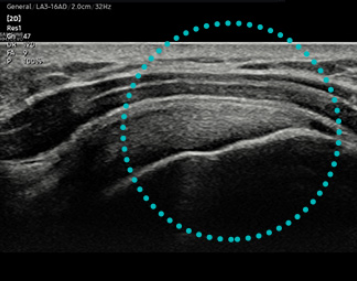

- Sonda Lineal LA3-16AD y Stick LS6-15.

HQ-Vision ™ proporciona imágenes claras al mitigar las características de las imágenes de ultrasonido que están ligeramente borrosas que la visión real.

El HM70 EVO admite una amplia gama de aplicaciones clínicas, entornos y tipos de pacientes, incluidos abdomen, cardíaco, vascular, musculoesquelético, mama, emergencia y piezas pequeñas. La versatilidad permite profesionales de la salud para desempeñarse eficazmente en exámenes específicos.